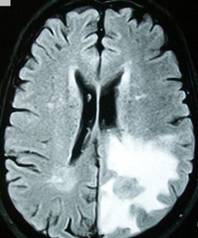

According to the definitive obituary in the Philadelphia Inquirer, his hometown paper, Sen. Specter, who died on Oct. 14 at age 82 from complications of non-Hodgkin’s lymphoma, first was stricken by cancer in the form of a brain tumor in 1993 (when he would have been about 63). After that came diagnosis and successful treatment of a second brain tumor in 1996, and treatment for Hodgkin’s lymphoma in both 2005 and 2008, followed by the non-Hodgkin’s cancer that led to his death.